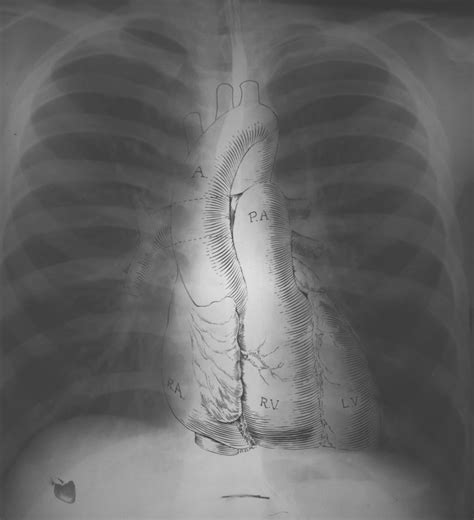

What Does a Normal Chest X-Ray Look Like?

Okay, so what exactly are doctors looking for when they say an X-ray is “normal”? Basically, a normal chest X-ray shows clear lungs, a heart of normal size and shape, and healthy-looking blood vessels. The bones, like your ribs and spine, should also appear intact and without any signs of fractures or abnormalities. Think of it like a well-organized room – everything is in its place, and there’s nothing out of the ordinary catching your eye.

The heart should appear in the center of the chest, slightly to the left. Its size and shape should be within normal limits. An enlarged heart, or cardiomegaly, can be a sign of heart failure or other cardiovascular problems. The heart’s borders should be well-defined, and there should be no unusual bulges or indentations. Doctors also assess the position and size of the great vessels , such as the aorta and pulmonary artery. Any abnormalities in these structures could indicate congenital heart defects or other vascular conditions. In addition to the heart itself, doctors also look at the surrounding structures, such as the pericardium (the sac that surrounds the heart). Inflammation of the pericardium, known as pericarditis, can cause fluid to accumulate around the heart, which may be visible on a chest X-ray. By carefully examining the heart and its surrounding structures, doctors can gain valuable insights into the patient’s cardiovascular health.